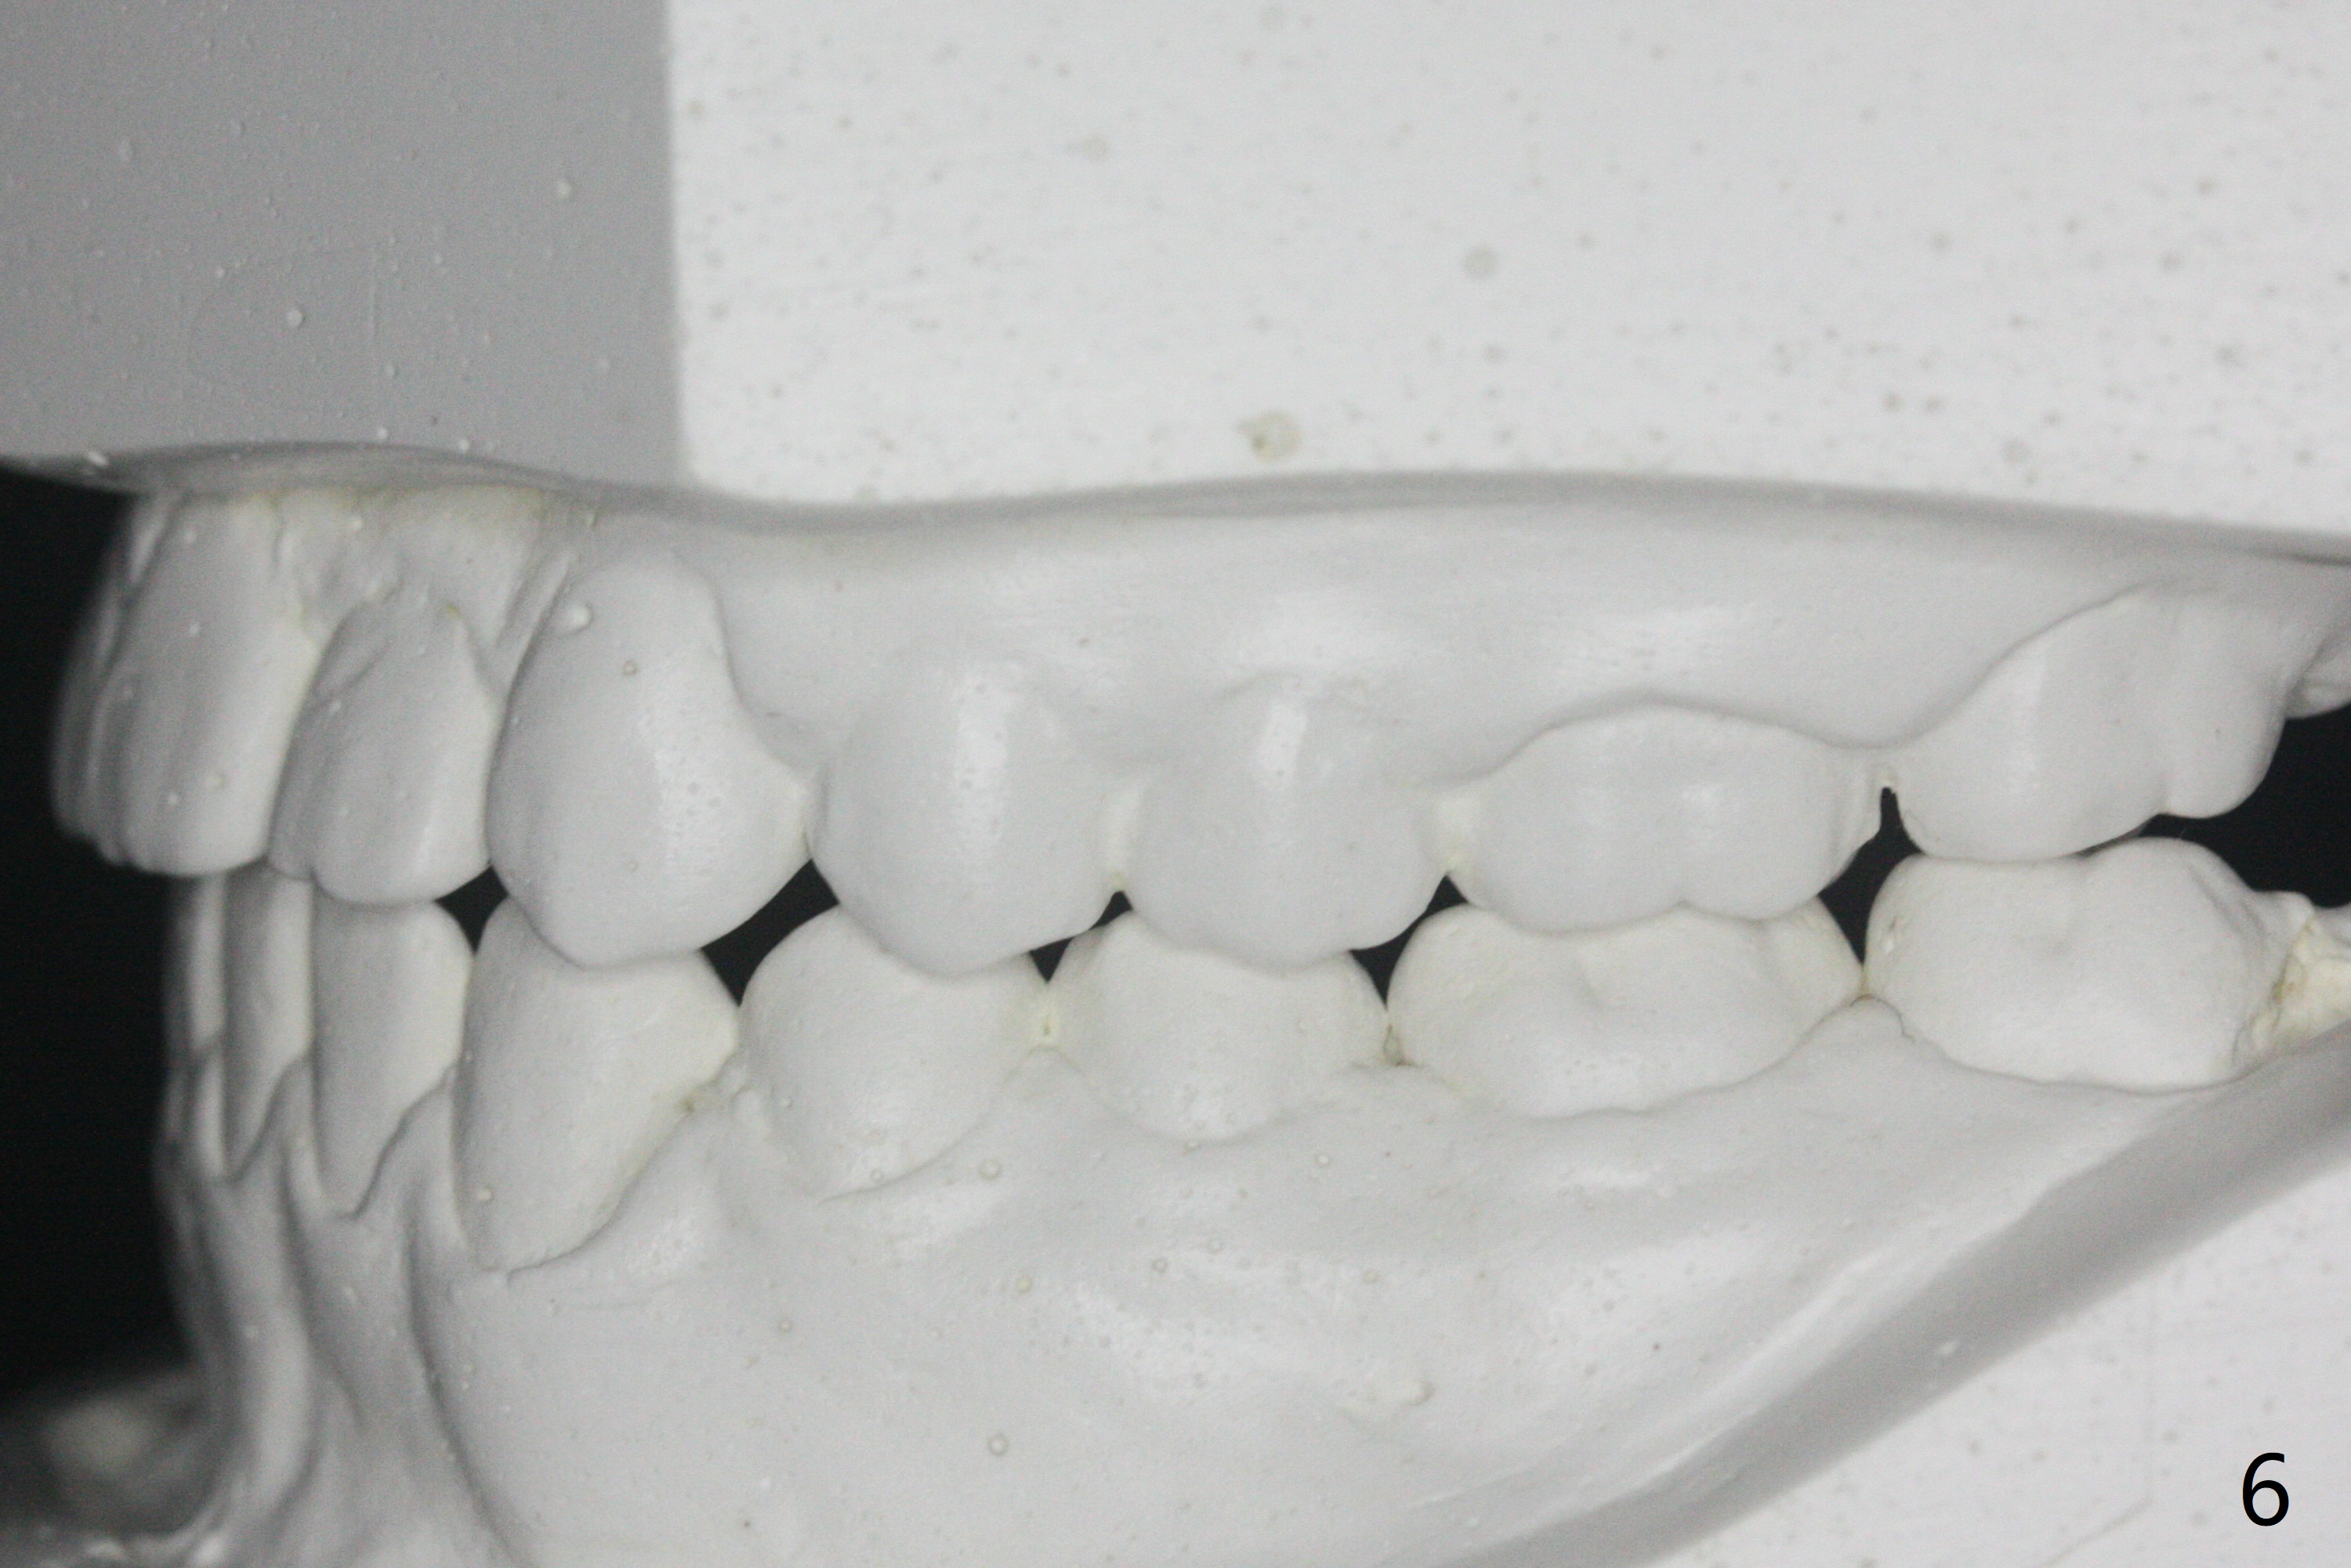

15岁男完成矫正1年9月,右侧后牙咬合理想(图二),上中切牙长轴改善,侧切牙torque不够完善(图四),左侧后牙咬合二类𬌗(图六,需要牵引),磨牙缝隙大(图八,十),造成食物堵塞,以后尽量避免使用磨牙bands,尤其是成人。